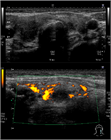

1. 甲状腺結節性病変に対して、超音波上の特徴的な所見を分析することで、良性結節をより的確に診断し、不必要な穿刺吸引細胞診を減らすことができる(推奨度2)

1. 超音波で悪性を疑う所見としては、縦横比>1(感度40.0%、特異度91.4%)、境界部棘状(感度48.3%、特異度91.8%)、著明な低エコー(感度41.4%、特異度92.2%)、微細石灰化(感度44.2%、特異度90.8%)、粗大石灰化(感度9.7%、特異度96.1%)であった(推奨度2)